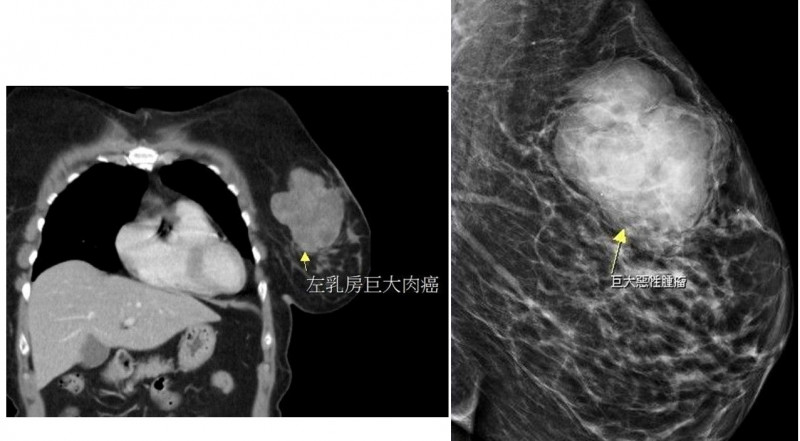

〔記者彭健禮/苗栗報導〕苗栗一位56歲黃姓婦女,數月前開始覺得左邊乳房觸摸起來有異狀,起初不以為意,但近日開始明顯摸到硬塊而且會疼痛,到大千綜合醫院就醫。外科部主任馮啟彥安排超音波檢查發現:黃女的左邊乳房有一個將近10公分大的腫瘤,原以為只是一般常見的乳腺癌,惟手術切除後,病理報告顯示,是罕見的肉癌。

馮啟彥表示,一般常見的乳癌是從乳房的腺體或是乳管長出來的腺癌,而肉癌則是因骨骼和軟組織病變而產生,例如:肌肉、脂肪、血管、神經、肌腱和關節內膜等。肉癌的發生率較罕見,可能出現在身體的任何部位,但以手臂、腿和腹部是較常見的部位,像此位病人長在乳房的更是少之又少。

此次病人的腫瘤非常大,也增加治療的困難度,所幸手術後病人恢復良好,病理報告也證實腫瘤已切除乾淨,目前持續密集追蹤狀況。馮啟彥提醒,若發現身體有異狀,務必要提早就醫,才能讓治療更加順利。